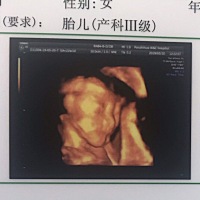

宝宝2个月啦!和四维像吗?😏